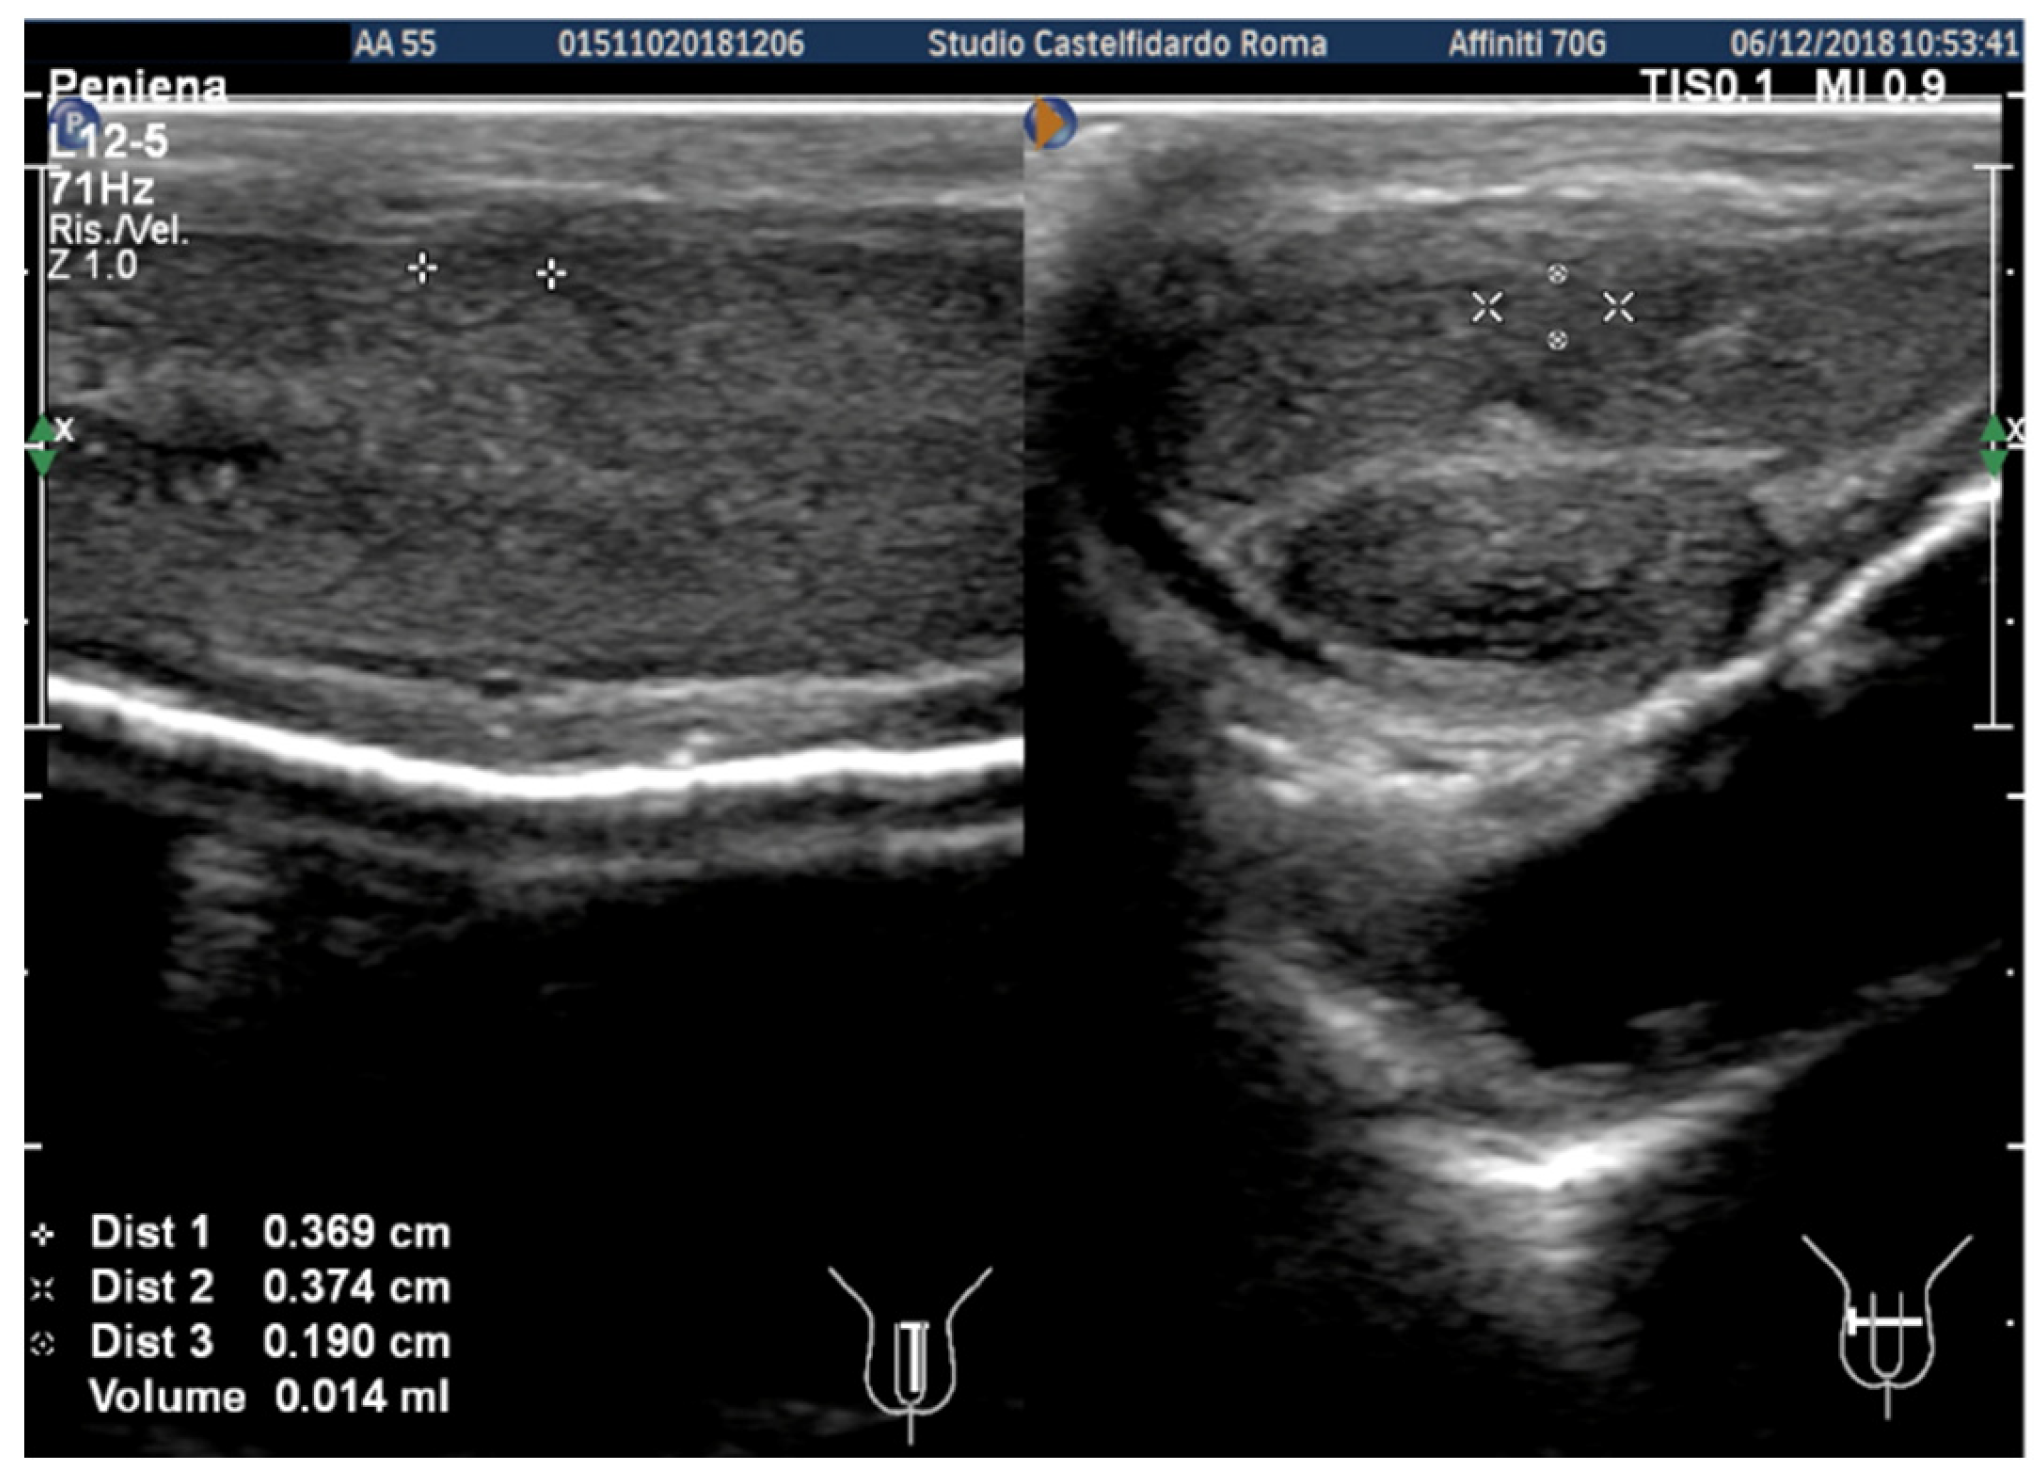

| No. | Patient Age | Associated Disease | Penile Plaque Site | Ultrasound Measurements (Length × Width × Thickness) and Plaque Volume before (A) and after Treatment (B) | Type of Deformity Initial (A) and after Treatment (B) | Pain Score/VAS Scale (1–10) | IIEF Score before and after Treatment | Total Duration of Treatment until Plaque Regression | Complete Combined Multimodal Treatment |

|---|---|---|---|---|---|---|---|---|---|

| 1 | 31 years | Chronic prostatitis and associated anxious and depressive state. | Distal third | (A) 15.1 × 12.1 × 3.7 mm volume = 353 mm3 (B) No plaque detected | (A) 10-degree ventral curvature + 15-degree left curvature (B) None | VAS score = 8 Pain disappeared after 12 months | 26 > 27 | 30 months | Orally: propolis 600 mg + bilberry 160 mg + silymarin 400 mg + ginkgo biloba 250 mg + L-carnitine 1000 mg + coenzyme Q10 100 mg + Boswellia 200 mg + Vitamin E 30 mg/daily/for 30 months + topically: diclofenac gel 4%/2× daily for 30 months Note: The patient refused periplaque penile injections with pentoxifylline |

| 2 | 52 years | Dupuytren’s disease, Ledderhose disease, congenital dorsal penile curvature (5 degrees). | Middle third + distal third | (A) First plaque: 13.4 × 9.15 × 2.83 mm volume = 182 mm3. Second plaque: 14.8 × 8.43 × 3.87 mm. Total volume = 252 mm3 (B) No plaque detected | (A) 20-degree dorsal penile curvature + 20-degree left penile curvature (B) 5-degree dorsal penile curvature. Previous condition = congenital dorsal penile curvature (5 degrees) | VAS score = 0 | 26 > 27 | 51 months | Orally: propolis 600 mg + bilberry 160 mg + silymarin 400 mg + ginkgo biloba 250 mg + L-carnitine 1000 mg + coenzyme Q10 100 mg + Boswellia 200 mg + vitamin E 30 mg/daily for 51 months + topically: diclofenac gel 4%/2× daily for 51 months + periplaque penile injections: pentoxifylline 100 mg (30 G needle) every 2 weeks for 6 months, and then 1 penile injection every month for 12 months, and 1 penile injection every 2 months for 24 months (42 total injections) |